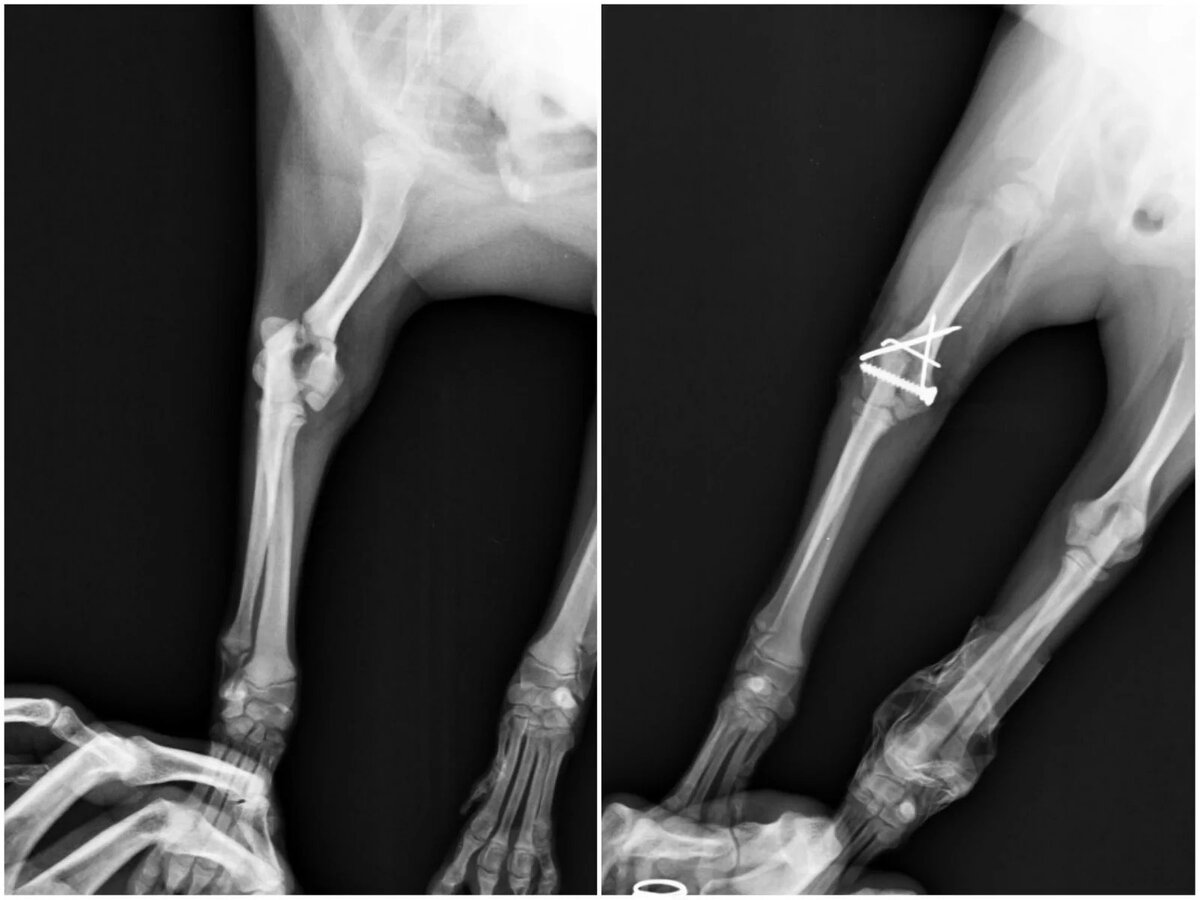

Переломы у собак (2 часть)🦴

Важно вернуть кость к ее первоначальной анатомической структуре.

Обеспечение стабильности кости критически важно для предотвращения ее смещения в процессе заживления.

В послеоперационный период важно обеспечить условия для эффективного заживления кости, позволяя фиксирующим конструкциям нести основную нагрузку. Оптимальное заживление, как правило, происходит в течение 6-8 недель, но это не исключает необходимости в ранней активации и поддержке функции поврежденной конечности. Ранняя опора на конечность важна для предотвращения атрофии мышц и способствует лучшему восстановлению. Также, реабилитация может включать посещение ветеринарного реабилитолога для оценки и коррекции функциональных ограничений, что помогает максимизировать восстановление подвижности и улучшить качество жизни животного после травмы.